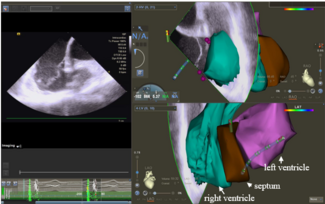

The authors report a precise endomyocardial biopsy procedure in a patient with unexplained heart failure under guidance of an electroanatomical mapping system, which can avoid the complications of cardiac tamponade and arrhythmias.